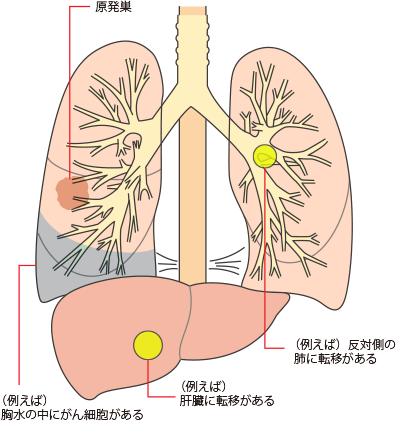

IV期(ステージ4)の肺がん:転移性肺がん

IV期(ステージ4)の肺がんとは

TNM分類でⅣ期と分類された肺がんは転移性がんとされています。

転移の中でも、肺から離れた臓器(肝臓、脳、骨など)や原発巣とは反対側の肺、胸膜や心膜に転移したもの(遠隔転移)があればIV期(ステージ4)と判定されます。組織型(腺がん、扁平上皮がん、大細胞がん、小細胞がん)やリンパ節転移の有無、原発のがんの大きさは問いません。

胸水(肺と胸壁の間にたまった水)や心嚢水(心膜と心臓の間にたまった水)の中にがん細胞がある場合もIV期(ステージ4)です。

IV期(ステージ4)の肺がんの治療

IV期(ステージ4)の肺がんは、多くの場合、手術は難しいため、治療方法は薬物療法が中心です。